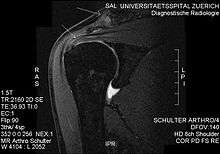

Plain x-rays of the shoulder can be used to detect some joint pathology and variations in the bones, including acromioclavicular arthritis, variations in the acromion, and calcification. However, x-rays do not allow visualization of soft tissue and thus hold a low diagnostic value.[1] Ultrasonography, arthrography and MRI can be used to detect rotator cuff muscle pathology. MRI is the best imaging test prior to arthroscopic surgery.[1] Due to lack of understanding of the pathoaetiology, and lack of diagnostic accuracy in the assessment process by many physicians,[11] several opinions are recommended before intervention.